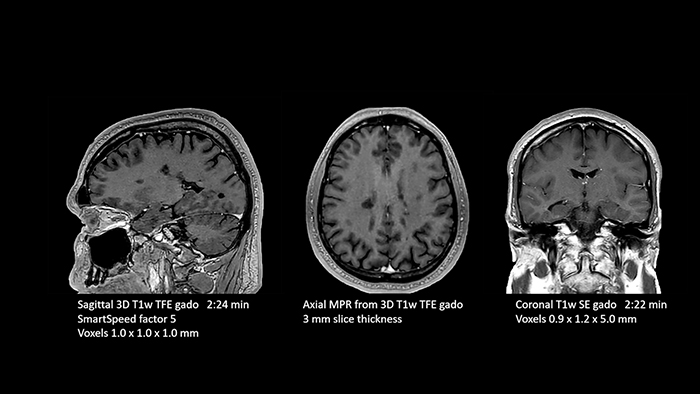

Dr. Tobias Schröter, MD, has been a radiologist since 2000. After running a 24/7 radiology practice for 16 years, he took over MRT-Praxis Potsdam, specializing in MRI diagnostics. “After the takeover, I completely redesigned the premises and exchanged the older MRI machine for a 1.5T Philips Ingenia Ambition S with sealed magnet.” Recently, the MRI Practice in Potsdam acquired AI-based Philips SmartSpeed of which Dr. Schröter has found that it makes a significant difference. “We had already been using Compressed SENSE from Philips to accelerate our cartesian scans and increase throughput. SmartSpeed now allows us to further reduce scan times and artificial intelligence (AI) makes the image quality even better compared to images we acquired using Compressed SENSE.” Dr. Schröter now uses SmartSpeed for 2D and 3D sequences in all anatomies. “I am astonished at the great potential of SmartSpeed, especially because 3D imaging in MSK is becoming feasible now. I can get very good image quality in very short scan time.” He also uses SmartSpeed for patients that cannot hold still, without worrying about needing re-scans. And it can also be used for patients with implants. “Besides the fast scanning, we now have the advantage of fast image reconstruction, so that we can already look at images while the scanning is still ongoing.”

MRT-Praxis Potsdam mostly focuses on neuro imaging and musculoskeletal examinations. They also perform prostate examinations, and occasionally some abdominal MRI. “Philips SmartSpeed really helps us scan more patients per day,” Dr. Schröter says. “We achieve higher throughput and better productivity without compromising on image quality. We used to scan 32 to 35 patients per day, but now with SmartSpeed we can perform significantly more examinations in less time. We went from 160 to 170 exams per week before SmartSpeed to up to 200 per week, or about 40 patients per day. “The short MRI scan times that we realize with SmartSpeed also provide better comfort for all our patients. Not everyone is comfortable lying in the scanner. Even normal, healthy individuals often cannot lie still for that long, which may lead to motion artifacts. So, being able to image faster is an obvious benefit. Our average examination time is now about 10 minutes. Only a few of our exams need more than 20 minutes.”

Then, because the computing capacity is so large, we have the images immediately available on the large screen. Higher resolution is very valuable. From the high-resolution 3D sequences, excellent multiplanar reconstruction can be obtained. This makes it easier and faster for us to diagnose and create reports. And while the patient is still lying in the magnet, we can already view the images and make a diagnosis. When the patient comes out, I can immediately ask whether what I see corresponds to the symptoms.”

Dr. Schröter points out that a more confident diagnosis requires high-quality images with more diagnostic information. “Philips SmartSpeed provided that to us. AI denoises the clinical images without losing any important data, resulting in high-resolution images. It keeps all the information we need and makes the images better. We can apply SmartSpeed to almost all sequences. That is a big step forward! We use it for example in 3D imaging and in diffusion-weighted imaging, to dramatically reduce scan time or increase image resolution, which is quite useful. There are small lesions that we would certainly have seen without SmartSpeed, however it would have taken us longer to properly diagnose. In 3D MSK images with extremely high resolution, we uncover the finest anatomical structures and can thus report very detailed findings.”